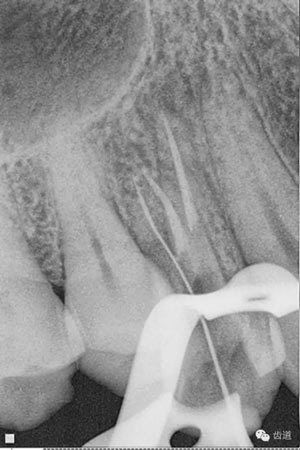

檢查顯示:近頰及腭根充填恰填,遠(yuǎn)頰根管內(nèi)有少許充填物影像。根尖明顯低密度影像。

處理:顯微根管治療。放置橡皮障,去除暫封,顯微鏡下超聲去除頰側(cè)根管上段部分牙本質(zhì),探及遠(yuǎn)中根管口,見(jiàn)有糊劑遮蓋。Path file根管疏通,M Two根管預(yù)備至2506#,配合3%次氯酸鈉和17%EDTA超聲蕩洗,干燥根管,放置氫氧化鈣糊劑,zoe暫封。